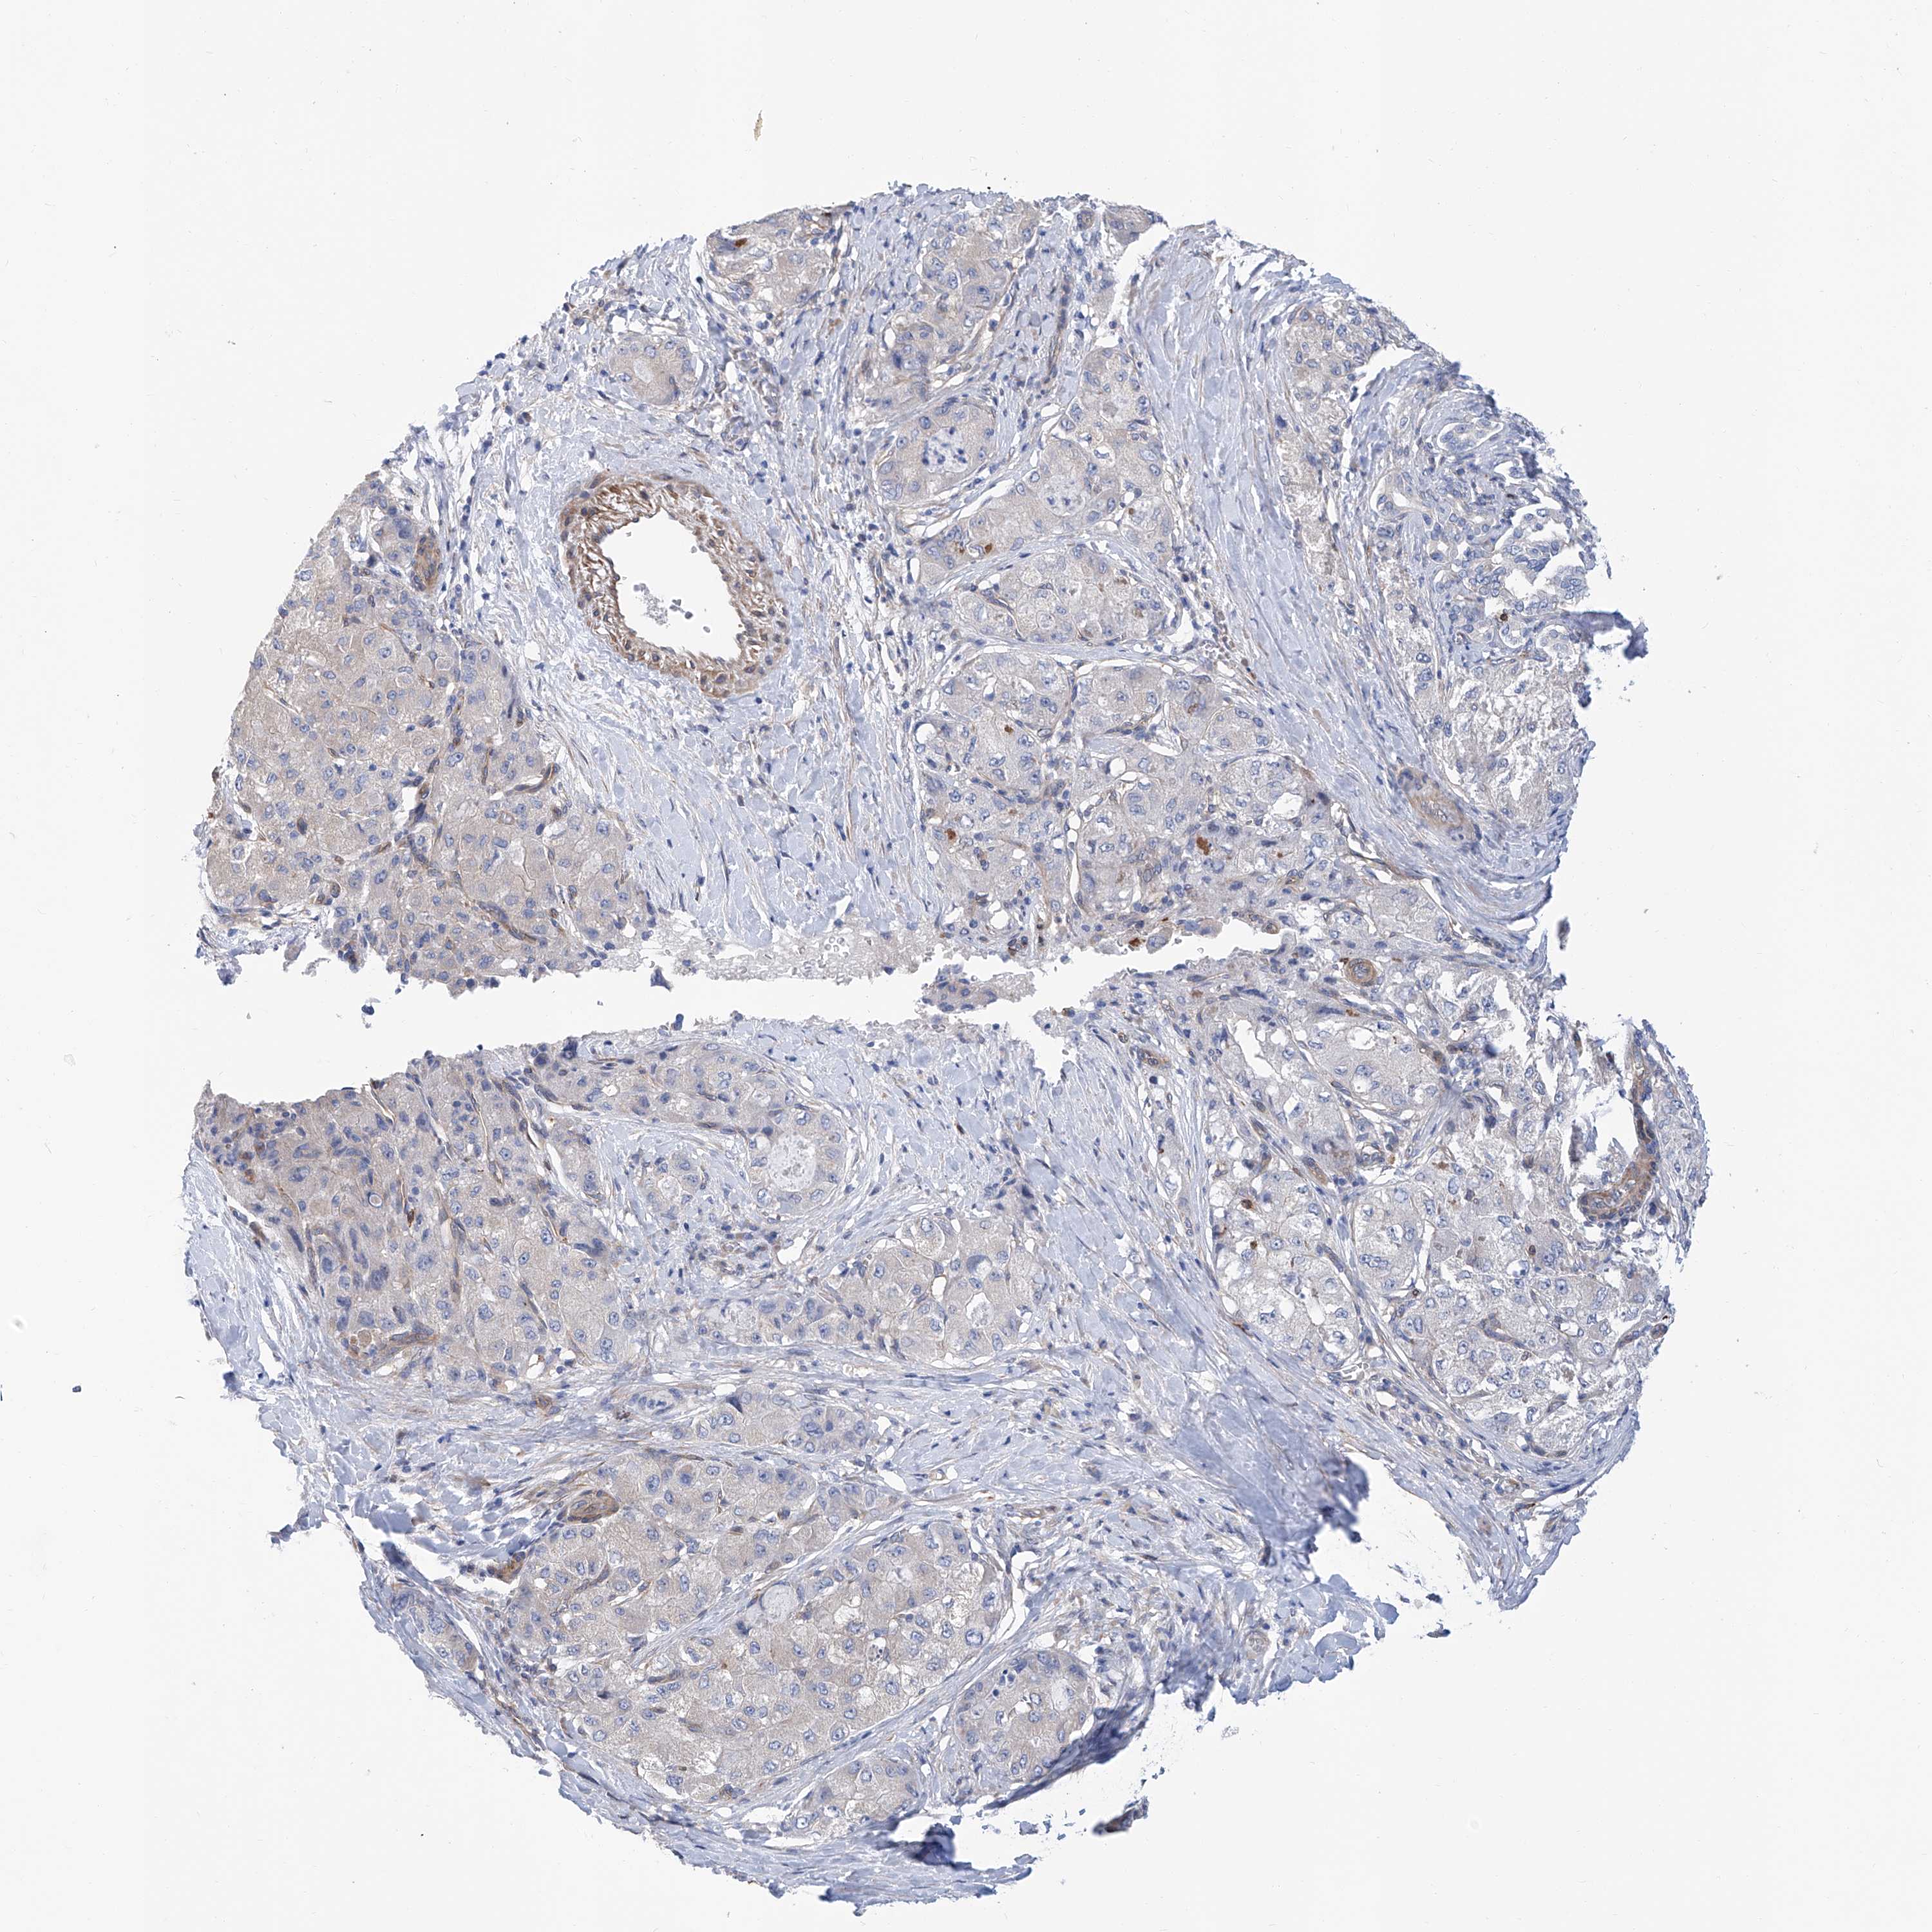

LIVER CANCER - Protein expressioni

A mouse-over function shows sample information and annotation data. Click on an image to view it in a full screen mode. Samples can be filtered based on level of antibody staining by selecting one or several of the following categories: high, medium, low and not detected. The assay and annotation is described here.

Note that samples used for immunohistochemistry by the Human Protein Atlas do not correspond to samples in the TCGA dataset.

Antibody stainingi

Antibody staining in the annotated cell types in the current human tissue is reported as not detected, low, medium, or high, based on conventional immunohistochemistry profiling in selected tissues. This score is based on the combination of the staining intensity and fraction of stained cells.

Each image is clickable and will lead to virtual microscopy that enables deeper exploration of all samples and also displays staining intensity scores, fraction scores and subcellular localization as well as patient and tissue information for each sample.

Antibody HPA026726

Antibody HPA026764

Antibody CAB010907

Staining

High

Medium

Low

Not detected

Intensity

Strong

Moderate

Weak

Negative

Quantity

>75%

75%-25%

<25%

None

Location

Nuclear

Cytoplasmic/membranous

Cytoplasmic/membranous,nuclear

Cholangiocarcinoma

Carcinoma, Hepatocellular, NOS